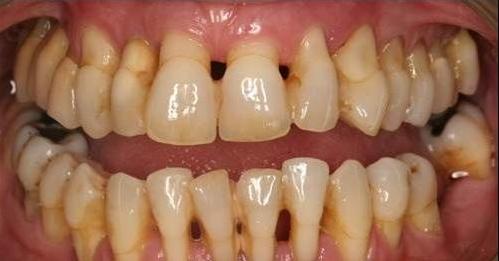

首先,牙龈退缩严重的患者,日常饮食都是很困难的,牙齿出现松动,咬合力会急剧下降。

其次,牙齿会有一段牙根暴露在外,容易对冷热反应敏感,降低牙齿的防蛀能力。

再次,牙龈萎缩之后,原本包围在内的牙根和牙周组织都会被暴露出来,引发牙周疾病。形成一个恶性循环。

- 牙龈萎缩的晚期,想要将牙龈恢复到健康状态就几乎不可能了。如果牙齿已经出现了松动,甚至有将要脱落的迹象,有时即使通过治疗也无法保住病牙。